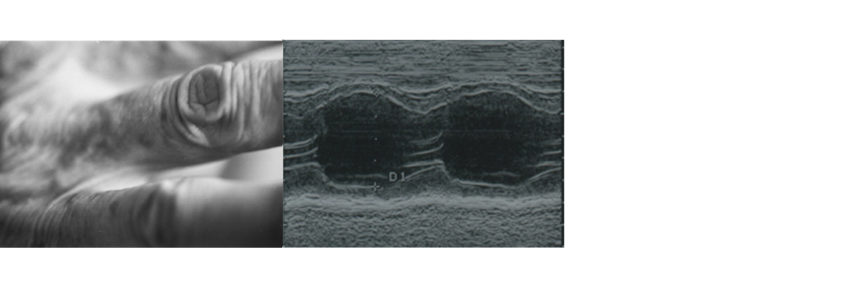

In questo progetto affianco fotografie di paesaggi terrestri, marini o lunari e fotografie di frazioni di corpi o immagini satellitari a scansioni interne al mio corpo: ecografie, risonanze, misurazioni a onde elettromagnetiche, analisi cromosomiche, doppler e radiografie. Nel corso dell’ultimo anno ho dovuto fare moltissime analisi ed ero molto incuriosita dalle sembianze che l’interno del mio corpo assumeva a seconda del tipo di indagine che veniva eseguita. Durante un eco-doppler delle vene guardavo nello schermo dello studio medico quella che sembrava una sonda spaziale che sorvola un pianeta extraterrestre, così è nato questo progetto in cui il corpo diventa un vero e proprio luogo da esplorare, protagonista di un viaggio alla scoperta di un’interiorità sconosciuta.